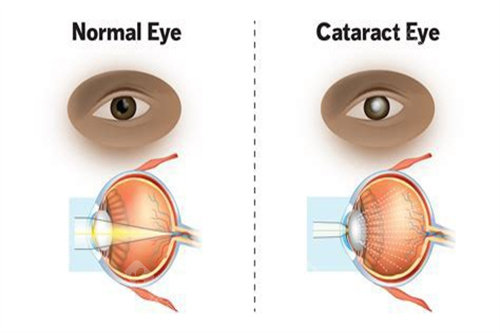

白内障是一种常见的眼科疾病,尤其在老年人群体中发病率较高。

当病情发展到一定程度,手术治疗是目前比较有效的方法。

医院采用的手术方式主要有超声乳化白内障吸除术联合人工晶状体植入术等,这些手术方式具有切口小、改善快等优点。